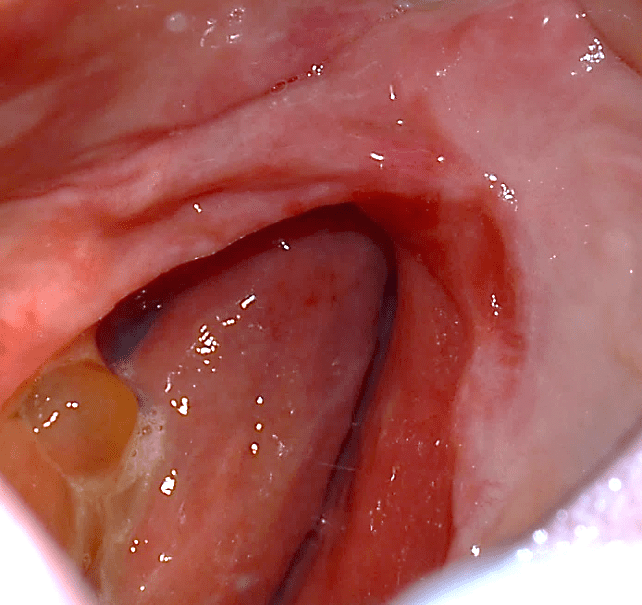

A 49-year-old female patient attended the prosthesis clinic at Nilton Lins University, mentioning dissatisfaction with her total obturator prosthesis, because she had a “broken front tooth” and the prosthesis was “falling”, emphasizing the desire to maintain the shape of the same. In the anamnesis reported that previously in 2012 he was diagnosed with mucoepidermoid carcinoma of intermediate degree in the palate (Appendix 1) and in 2013 after performing surgical removal and performing new tests, who did not indicate the presence of malignancy (Appendix 2), was attested as cured, besides being hypertensive and using the drugs losartan potassium 50 mg twice daily and levanlodipine besidate 2.5 mg once a day. No alterations were observed on extraoral clinical examination. In the intraoral clinical examination, there was absence of the upper arch teeth, bucosinusal communication and partial maxillary edge and in the lower region only the presence of teeth 31, 32, 33, 41, 42, 43, 44 and 45 (figures 1 and 2).

Figure 1: Surgical defect of the upper arch.

After three months using the obturator prosthesis, new control tests were performed, and immediate surgical intervention was necessary, because the neoplastic lesion had recurs (figure 22). On the patient’s return, after the first surgery (figure 23) and with the result of the histopathological examination (Appendix 3), which indicated margin involvement. The medical team intervened and elaborated another treatment plan, which consisted of surgical removal with margin enlargement. In a new dental visit, twelve days after the second surgery (figure 24), the histopathological examination again indicated compromised margins (Appendix 4). Therefore, a more invasive surgery was planned by the medical team, which may lead to facial involvement.

Figure 22: Recurrence of the lesion.

Figure 23: Surgical step 1 of removal.

Figure 24: Surgical step 2 of removal.